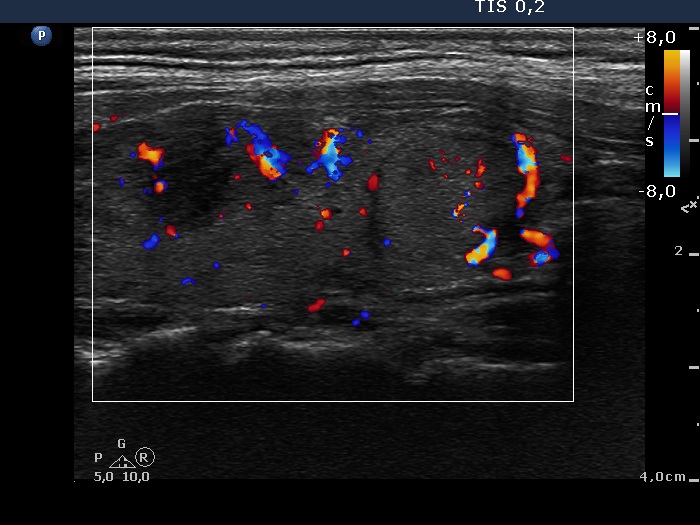

Discrete lesion or nodule in Hashimoto's thyroiditis - case 10 (95) (ultrasonographic picture 10)

Left lobe, longitudinal scan, color Doppler mode. The nodule in the lower pole displays perinodular blood flow.